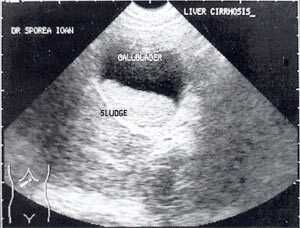

В исследовании, проведенном в США, "желчный сладж" выглядел в виде гиперэхогенного образования в желчном пузыре с горизонтальным уровнем без задней тени, форма которого медленно изменялась при движении больного [10]. Характерный признак "желчного сладжа" - изменение его вида на сканограмме в зависимости от изменения положения тела больного и медленным достижением нового горизонтального уровеня. Общим правилом является отсутствие дистальной акустической тени. Эхогенность сладжа может быть различной. Иногда сладж заполняет весь желчный пузырь, затрудняя дифференцировку между тканью печени и желчным пузырем. Эта ситуация называется "гепатизация желчного пузыря" (рис. 1).

Кроме типичного вида, "желчный сладж" может иметь особый вид, похожий на круглое полипоидное объемное образование с острыми краями или неравномерным контуром ("опухолеподобный желчный сладж" или "сладжевые шарики" [12, 13]). При изменении положения больного видны перекатывающиеся или разрушающиеся шарики сладжа, затем снова формирующие исходное объемное образование (рис. 2-8).

Рис. 5. Желчный пузырь, заполненный сладжем, у больного циррозом.

Рис. 6. Желчный пузырь и "желчный сладж".

Рис. 7. "Желчный сладж" в виде шара.

Рис. 8. Шароподобный "желчный сладж".